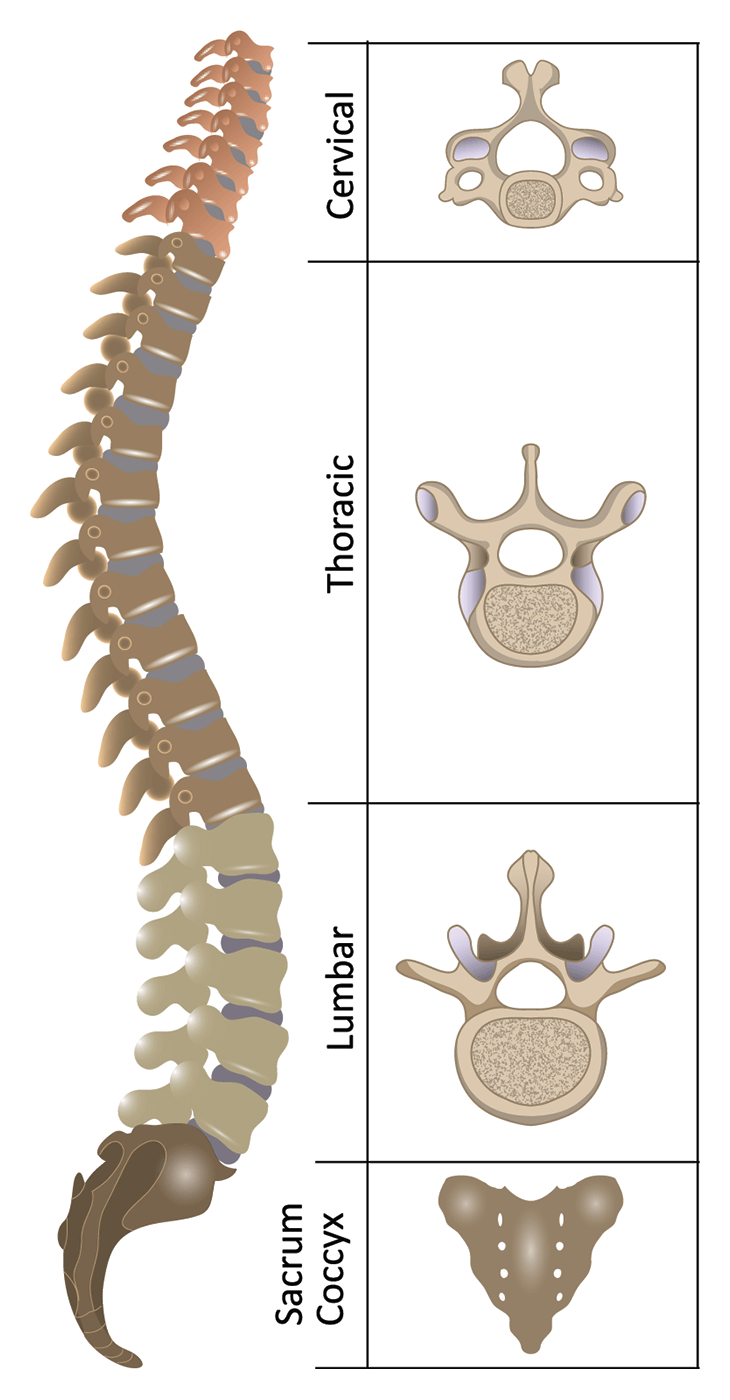

Here the spine is concave, curving toward the belly (lordotic). This area is very flexible and a common location of injuries. Vertebrae can be grouped into four groups: a. Injuries to the bones, ligaments or joints The spine connects to the hip bones at the sacro-iliac joints via a complex arrangement of ligaments.Strain of the large muscles of the back that hold the spine upright.Irritation of the smaller nerves of the spine that involve innervate or supply the discs between the vertebrae, facets and ligaments.Irritation of the large nerves as they exit the bony confines of the spine leading to the arms and legs.While many of us take the benefits of a healthy spine for granted, spinal pain is a sharp reminder of how much we depend on our back in daily life. The spinal column combines strong bones, unique joints, flexible ligaments and tendons, large muscles and highly sensitive nerves. Five bones in the lower back-the lumbar spine.

12 bones in the chest-the thoracic spine.Seven bones in the neck-the cervical spine.The remaining small bones or ossicles below the sacrum are also fused together and called the tailbone or coccyx. The spine is divided into four regions which contain vertebrae: the cervical, the thoracic, the lumbar, and the sacral.Hover over each part to see what they do. Vertebrae are numbered and named according to where they are located in the spinal cord. It is made up of several vertebral bodies usually fused together as one. Interactive Parts of the Spine & Vertebrae Sections. The bottom of the spine is called the sacrum. Sometimes a person may have an additional vertebra, which is called a transitional body and is usually found at the sixth level of the lumbar area (labeled L6). These vertebrae protect the brain stem and the spinal cord, support the skull and allow for a wide range of head movement. By the time a person becomes an adult most have only 24 vertebrae because some vertebrae at the bottom end of the spine fuse together during normal growth and development. The average person is born with 33 individual bones (the vertebrae) that interact and connect with each other through flexible joints called facets. The spine is composed of 33 bones, called vertebrae, divided into five sections: the cervical, thoracic, and lumbar spine sections, and the sacrum and coccyx. The spine supports about half the weight of the body. Structural support for the body, allowing us to stand upright.

It provides several important functions, including: The human spine is a complex anatomic structure that is the scaffolding for the entire body.